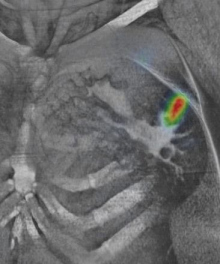

El 99mTc-tilmanocep (Lymphoseek, Navidea Biopharmaceuticals) es un nuevo radiotrazador para mapeo linfático intraoperatorio que ha sido aprobado recientemente por la Food & Drug Administration (FDA) de EEUU. El procedimiento está indicado en pacientes con cáncer de mama o melanoma que serán sometidos a linfadenectomía para remover el o los ganglios linfáticos que drenan el tumor primario (ganglios centinelas). El mapeo linfático intraoperatorio (el cual se puede realizar utilizando una sonda gamma o mediante una gamma-cámara portátil por un médico nuclear entrenado) es ampliamente utilizado para la estadificación de pacientes con cáncer de mama y melanoma que se presentan clínicamente (esto es, por exploración física y algunos estudios imagenológicos) sin enfermedad ganglionar. El procedimiento puede detectar con gran precisión si algún ganglio linfático contiene células tumorales (es decir, compromiso tumoral microscópico que escapa a la resolución de los estudios de imagen médica), ayudando así a la elección del plan de tratamiento más adecuado.

La aprobación por la agencia norteamericana está sustentada por datos de ensayos clínicos que agrupan a 332 pacientes con melanoma o cáncer de mama. A todos los pacientes se les inyectó Lymphoseek y azul patente y seguidamente los cirujanos removieron los ganglios linfáticos marcados por dichos trazadores para proceder a su examen histopatológico. En la confirmación histológica, los resultados mostraron que tanto el Lymphoseek como el azul isosulfán detectaron la mayoría de los ganglios linfáticos considerados “centinelas”, aunque un número significativo de ganglios fueron localizados únicamente con Lymphoseek (es decir, tuvo una mayor tasa de detección y menor tasa de falsos negativos).

Cabe mencionar que el 99mTc-tilmanocep no es un radiotrazador dirigido hacia las células tumorales, ni tampoco se trata de partículas marcadas que se fagocitan por los macrófagos ganglionares, sino que se une a los receptores de manosa de la superficie de las células de los ganglios linfáticos luego de ser inyectado alrededor del tumor primario. De este modo, el radiofármaco es retenido en el ganglio y se ha determinado en ensayos clínicos su superioridad respecto al colorante azul patente y a los coloides marcados.